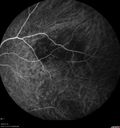

Syphillitic Optic Neuropathy and Maculopathy543 views46 year old woman with 2 weeks of vision loss OD. VA 20/200 OD; 20/20 OS. there are posterior vitreous cells on OCT in both eyes. ICG, FAF, and FA show an abnormal macula OD. VA improved to 20/30 within a month with treatment with PCN.

Syphillitic Optic Neuropathy and Maculopathy542 views46 year old woman with 2 weeks of vision loss OD. VA 20/200 OD; 20/20 OS. there are posterior vitreous cells on OCT in both eyes. ICG, FAF, and FA show an abnormal macula OD. VA improved to 20/30 within a month with treatment with PCN.

Syphillitic Optic Neuropathy and Maculopathy532 views46 year old woman with 2 weeks of vision loss OD. VA 20/200 OD; 20/20 OS. there are posterior vitreous cells on OCT in both eyes. ICG, FAF, and FA show an abnormal macula OD. VA improved to 20/30 within a month with treatment with PCN.

Syphillitic Optic Neuropathy and Maculopathy523 views46 year old woman with 2 weeks of vision loss OD. VA 20/200 OD; 20/20 OS. there are posterior vitreous cells on OCT in both eyes. ICG, FAF, and FA show an abnormal macula OD. VA improved to 20/30 within a month with treatment with PCN.

Syphillitic Optic Neuropathy and Maculopathy518 views46 year old woman with 2 weeks of vision loss OD. VA 20/200 OD; 20/20 OS. there are posterior vitreous cells on OCT in both eyes. ICG, FAF, and FA show an abnormal macula OD. VA improved to 20/30 within a month with treatment with PCN.

Syphillitic Optic Neuropathy and Maculopathy497 views46 year old woman with 2 weeks of vision loss OD. VA 20/200 OD; 20/20 OS. there are posterior vitreous cells on OCT in both eyes. ICG, FAF, and FA show an abnormal macula OD. VA improved to 20/30 within a month with treatment with PCN.

Syphillitic Optic Neuropathy and Maculopathy496 views46 year old woman with 2 weeks of vision loss OD. VA 20/200 OD; 20/20 OS. there are posterior vitreous cells on OCT in both eyes. ICG, FAF, and FA show an abnormal macula OD. VA improved to 20/30 within a month with treatment with PCN.

Syphillitic Optic Neuropathy and Maculopathy492 views46 year old woman with 2 weeks of vision loss OD. VA 20/200 OD; 20/20 OS. there are posterior vitreous cells on OCT in both eyes. ICG, FAF, and FA show an abnormal macula OD. VA improved to 20/30 within a month with treatment with PCN.

Syphillitic Optic Neuropathy and Maculopathy491 views46 year old woman with 2 weeks of vision loss OD. VA 20/200 OD; 20/20 OS. there are posterior vitreous cells on OCT in both eyes. ICG, FAF, and FA show an abnormal macula OD. VA improved to 20/30 within a month with treatment with PCN.